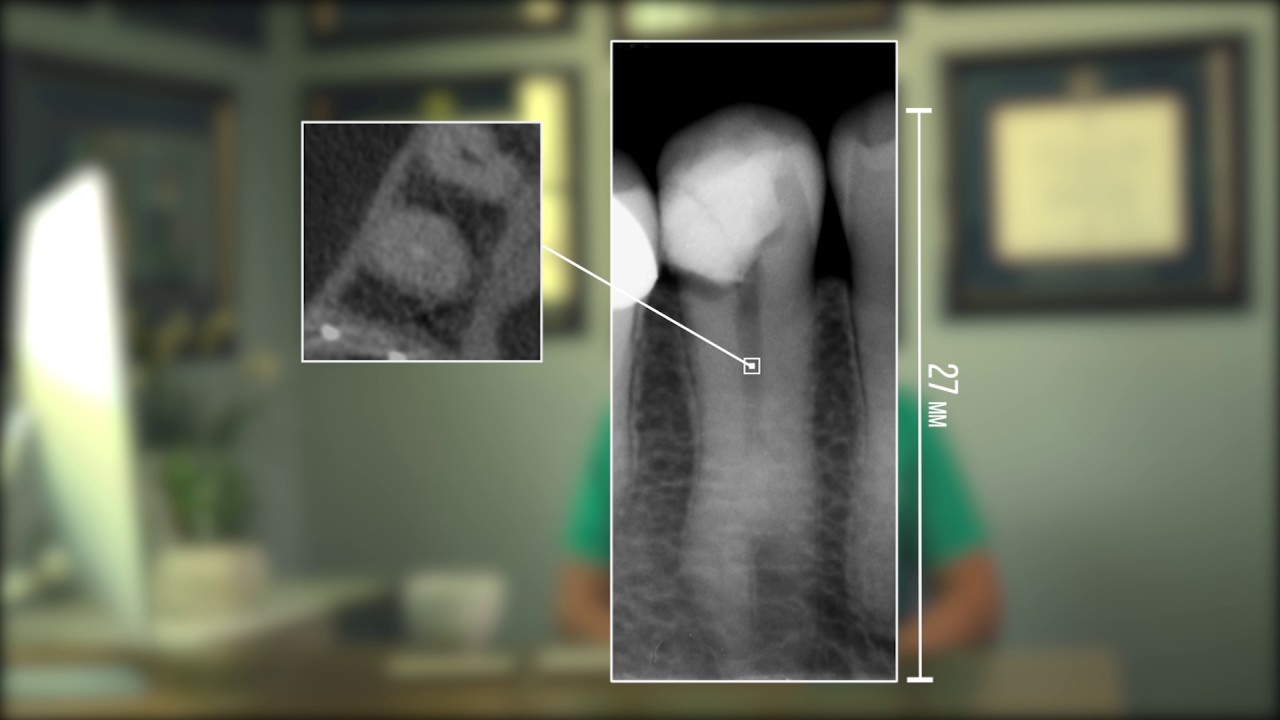

The value of the CBCT in the endodontic practice Endodontic Practice